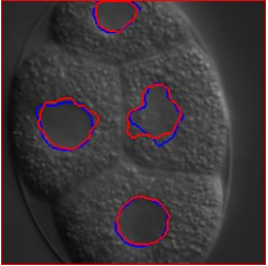

学習時には正しく領域を抽出できる場合でも、撮影条件が変化すると同じモデルでは対応できないことがあります。

例えば、対象や顕微鏡が同じでもカメラなどが異なるだけで、予測精度は大きく低下します(青:正解データ,赤:推定結果)。